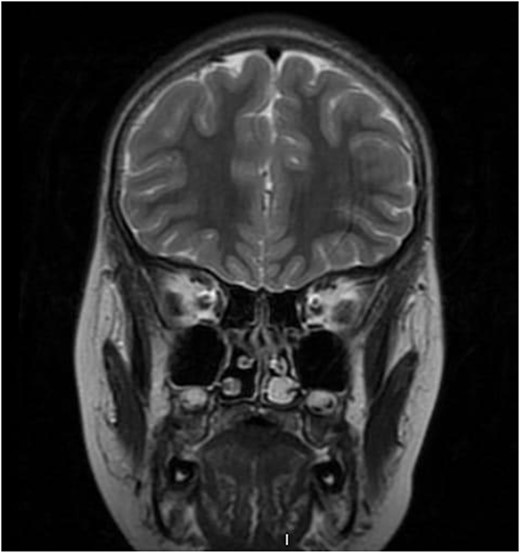

We present a case of a medically free 13-year-old male, who presented to the emergency department with a left-sided epistaxis for 2 days. Notably, the episodes of epistaxis resolve spontaneously after 5 to 10 min, without applying pressure. Also, the patient complained of on and off left-sided nasal obstruction, and denied history of dizziness, loss of consciousness, and choking. Upon physical examination, the patient was vitally stable, looking well, not cyanosed, nor having cervical lymph node enlargement. Nasal speculum examination showed left intra-nasal mass obstructing the cavity. Routine laboratory investigations yielded a hemoglobin (Hgb) level 0f 141g/L, white blood cell count of 7.30 K/μl, INR of 1.02, prothrombin time (PT) of 11.40 s, and partial thrombin time (PTT) of 28.30 s. Initially, the patient was radiologically investigated by paranasal sinuses (PNS) computed tomography (CT) which demonstrated an enhancing lesion involving the left nasal cavity. An MRI was performed demonstrating an oval-shaped mass filling the anterior nasal cavity, the lesion was measuring ~3 × 1.1 × 2.5 cm in anteroposterior, transverse, and craniocaudal dimension, respectively (Fig. 1). Intra-operative nasal cavity along with postnasal space examination was decided to be performed along with left nasal mass excisional biopsy under general anesthesia. Intraoperative examination of the nasal cavity using a zero-degree rigid endoscope showed a fragile left nasal mass (Fig. 2). The lesion was bleeding heavily; thus, cauterization was performed to control bleeding before taking the biopsy. The patient had an uneventful postoperative course. Histopathological evaluation showed the characteristic polypoidal lesion composing of capillary proliferation in a background of fibromyxoid stroma and granulation tissue, arranged in a lobular pattern.

Pre-operative coronal T2-weighted brain MRI showing high signal intensity left-sided intra-nasal lesion.